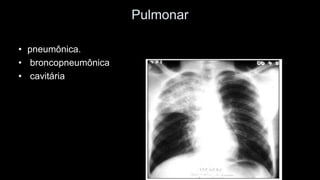

Pulmonar

•pneumônica.

•broncopneumônica

•cavitária